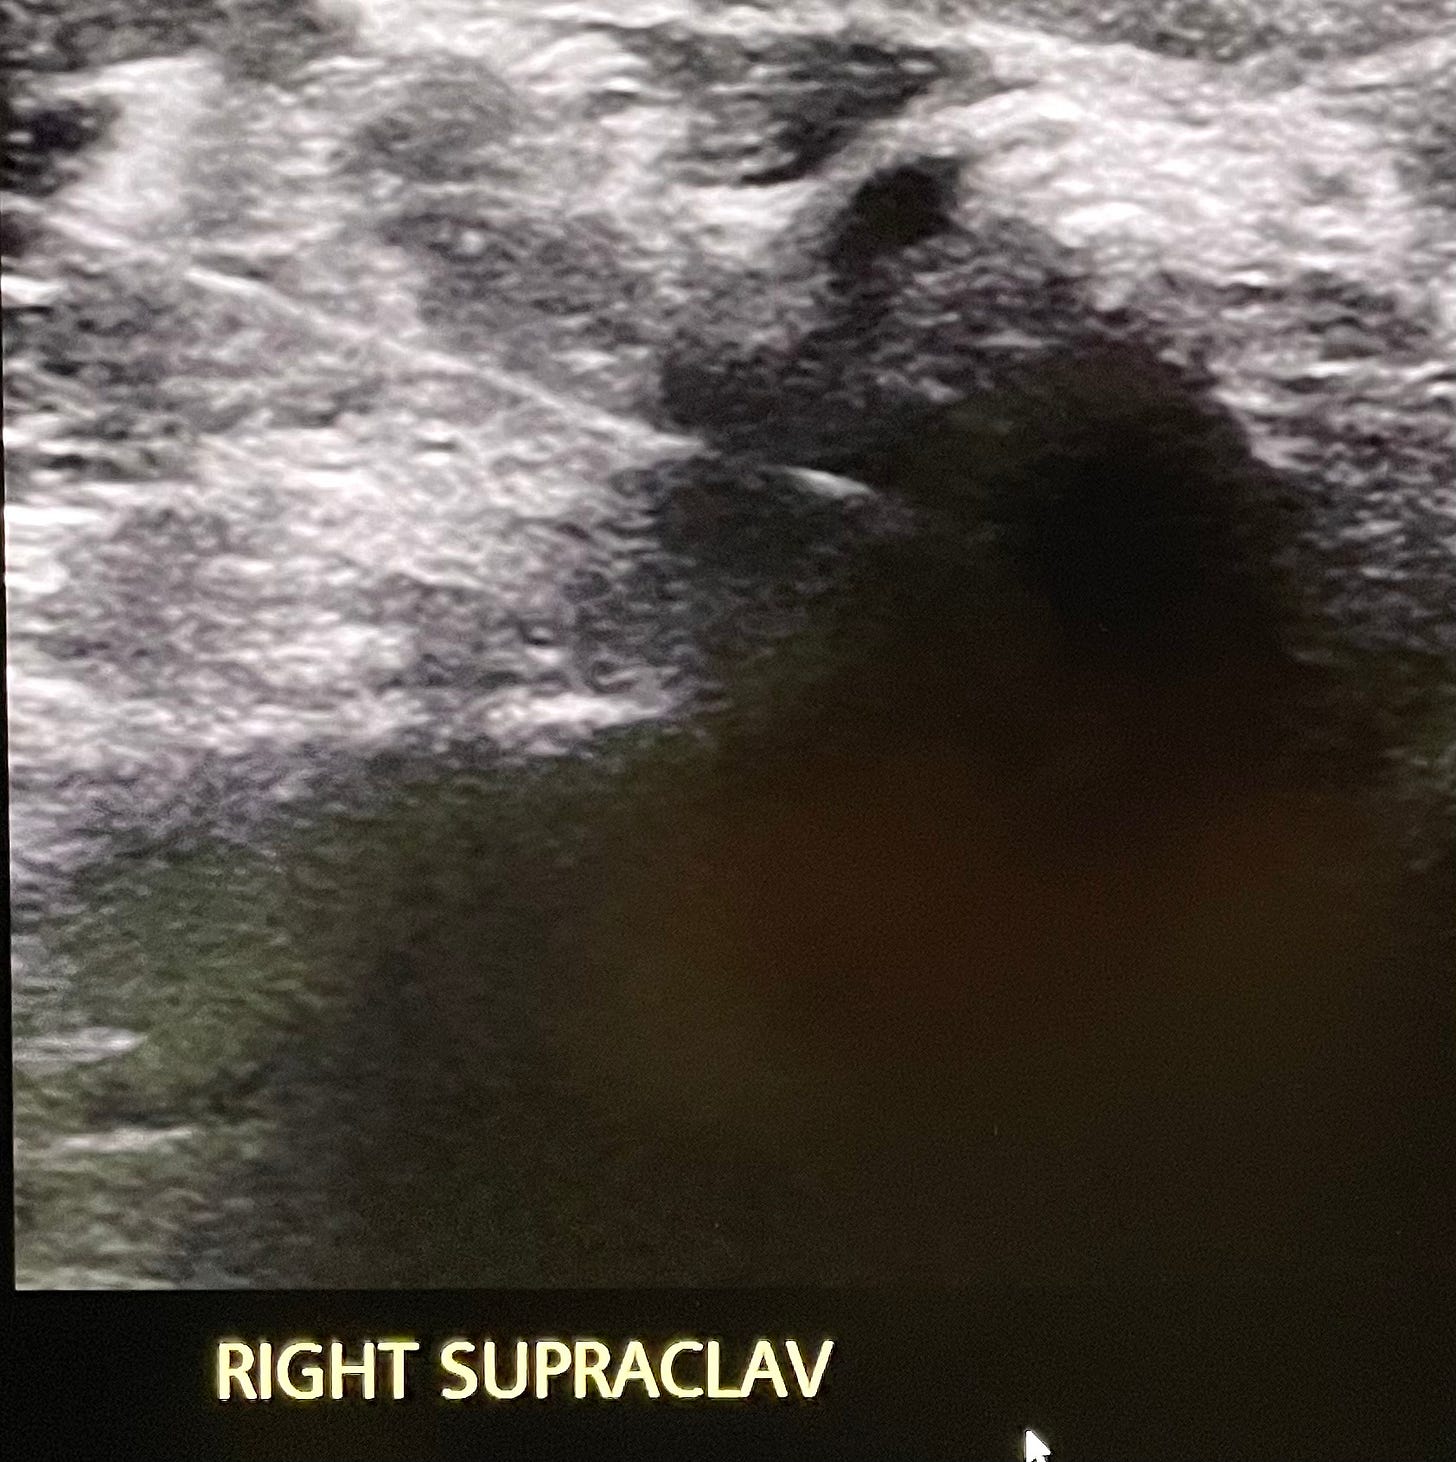

A trio of doctors were tasked with carefully inserting a hollow needle into the right side of my neck, searching for hotspot of cells to extract tissue samples for lab testing.

Like a Special Ops SWAT team equipped with night vision cameras, they used the guidance of a high resolution, realtime ultrasound image to probe my neck, navigating through its jungle of nerves, radiation-scarred tissue, re-plugged veins and arteries, past several surgical clips floating in suspension from a previous operation.